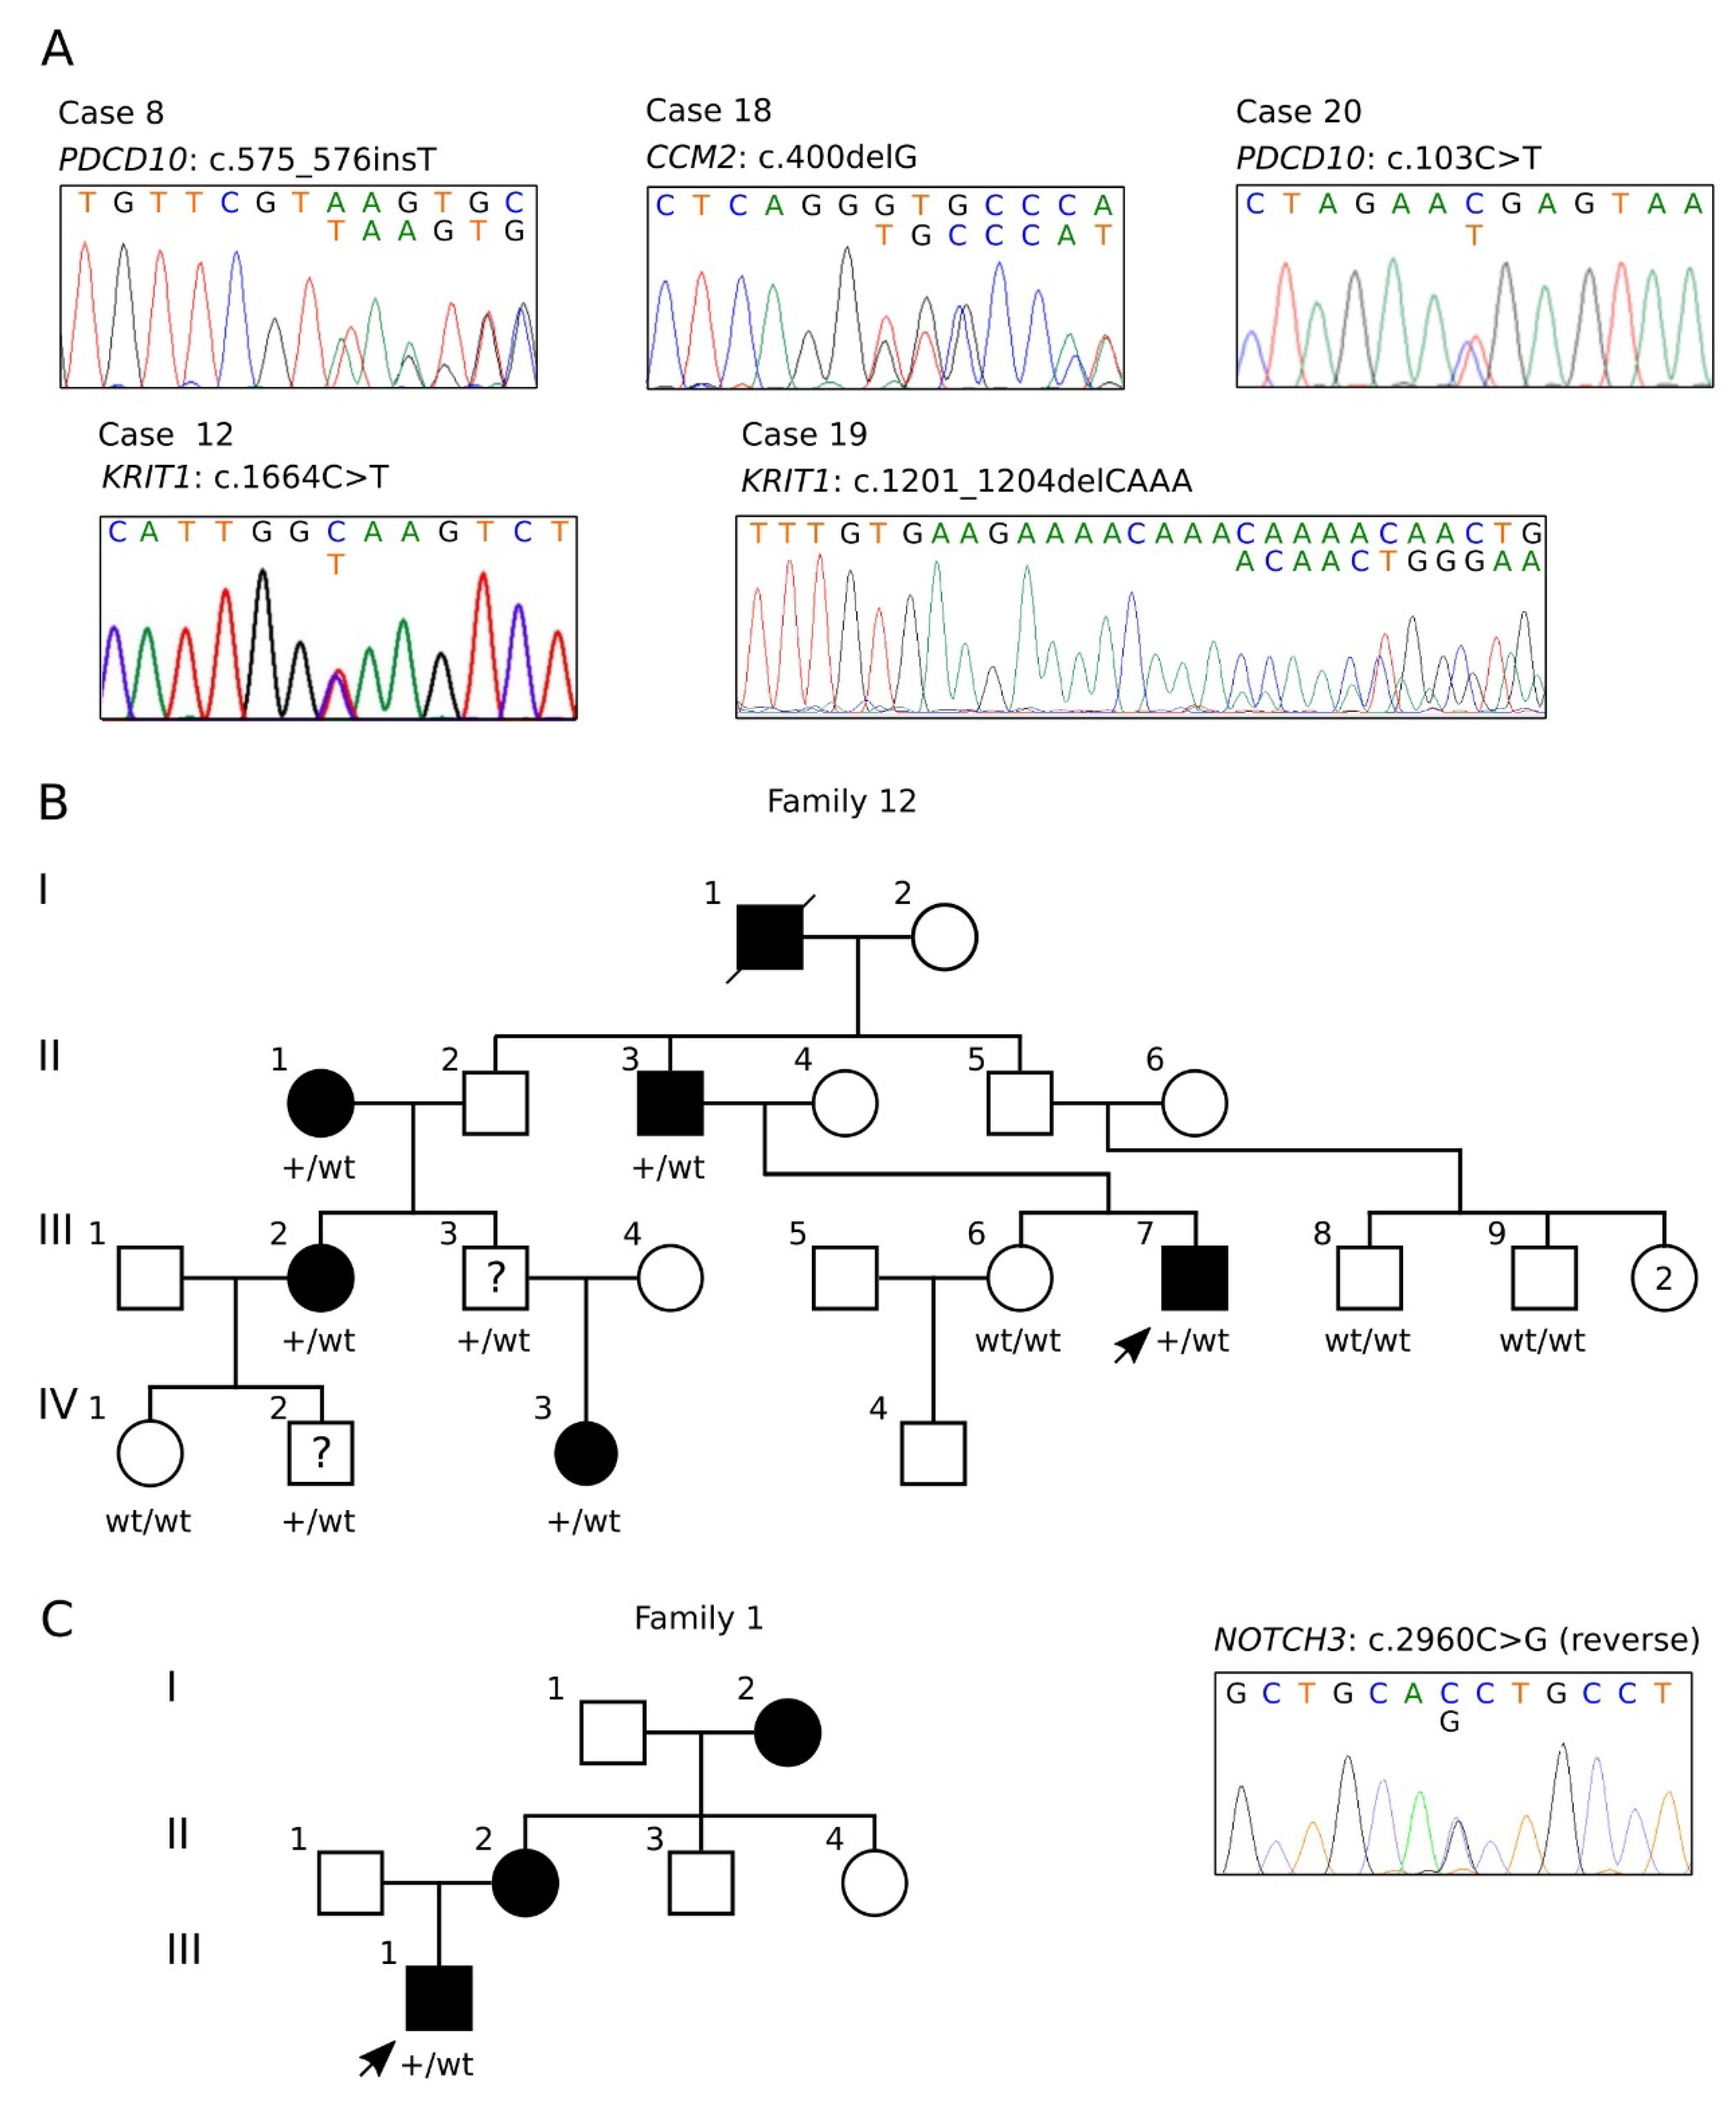

3.2. Characterization of the KRTI1 Genomic Deletion Identified in Case #7